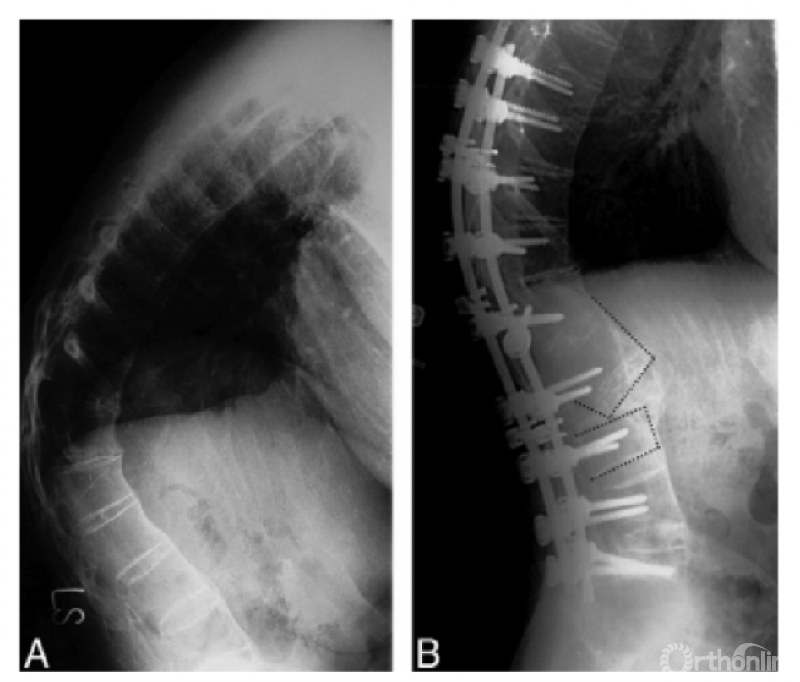

Cage

Hu等提出在PSO治疗AS胸腰椎后凸畸形过程中,截骨间隙内放置cage可有效降低ST的发生风险(cage组ST发生率4.7%vs.非cage组ST发生率30.4%,χ2=10.020,P=0.002)。cage置入截骨间隙后即刻发生下沉入头端和尾端的椎体松质骨内,可作为截骨间隙闭合过程中的铰链,能够有效限制头尾端椎体的移位,降低前皮质骨折断裂后的ST发生风险。

Cheng等通过截骨平面CT断层扫描观察到16例AS患者截骨后发生ST的椎管重塑形,椎管重塑形发生率100%,ST显著减小。

关于ST的椎管自发性重塑形的发生机制目前尚不得而知,可能与在钉棒的提拉作用下骨质顺应力学方向的生长,也可能与AS患者较强的骨融合能力有关,表现为截骨区的椎体闭合部能够自发的塑形重建。